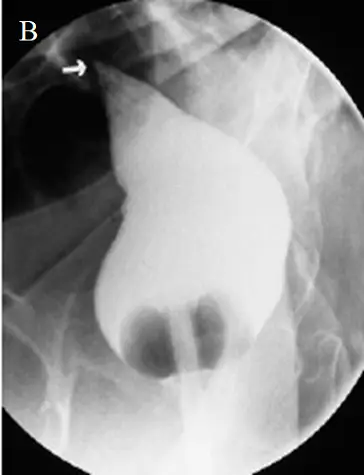

75歲老人由療養院送來,主訴腹脹,腹部X光片如圖(A),下消化道鋇劑攝影如圖(B),則其最可能的診斷為下列何者?

圖 B(下消化道鋇劑灌注造影)

- 鋇劑自直腸注入後,沿結腸中線向上推進至扭轉處突然變細,呈現平滑的錐狀收縮端,俗稱 “bird’s beak” 或 “bird-of-prey sign” ([jamanetwork.com](https: